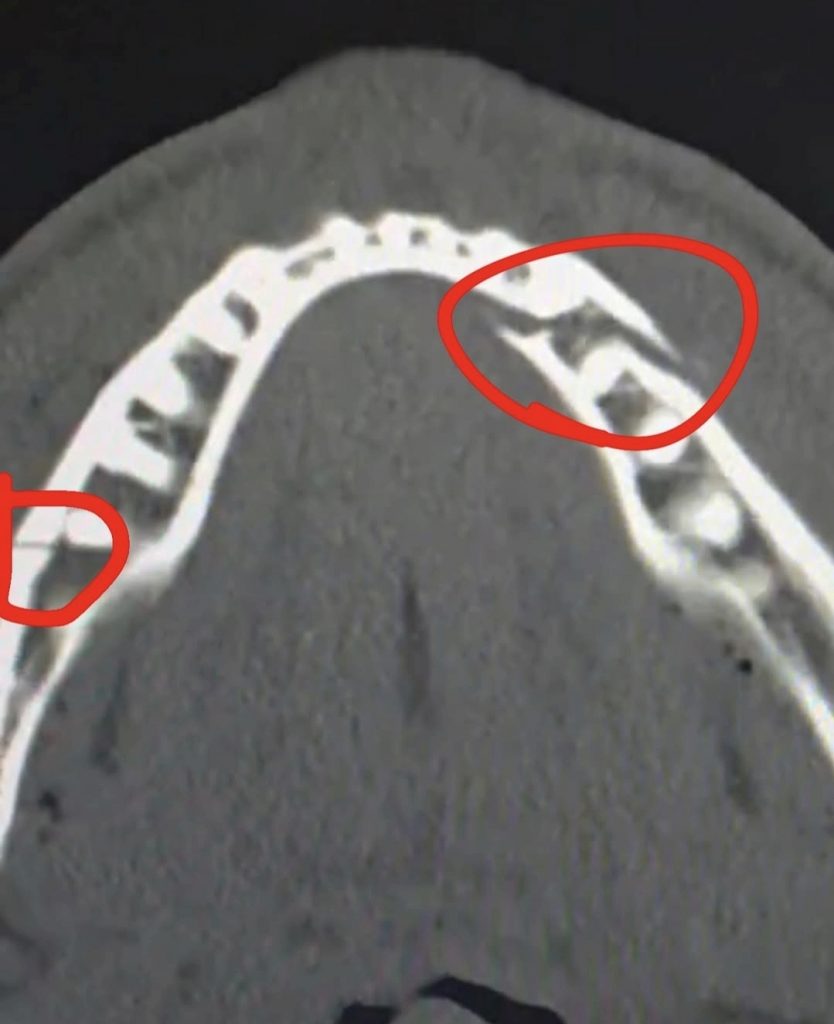

Pas përballjes, Jake Paul u shfaq i gjakosur, por sportiv në deklarata. “Ishte një mësim i fortë nga një prej më të mirëve të historisë. E pranova me kënaqësi,” tha ai. Më vonë, Paul konfirmoi se kishte pësuar thyerje të dyfishtë të nofullës dhe iu nënshtrua një ndërhyrjeje kirurgjikale. Megjithatë, ai nuk e humbi humorin dhe në një postim në Instagram shkroi me shaka “Ma sillni Canelo-n pas 10 ditësh”, duke ironizuar mbi gjendjen e tij dhe duke dërguar sërish një mesazh sfidues për botën e boksit.